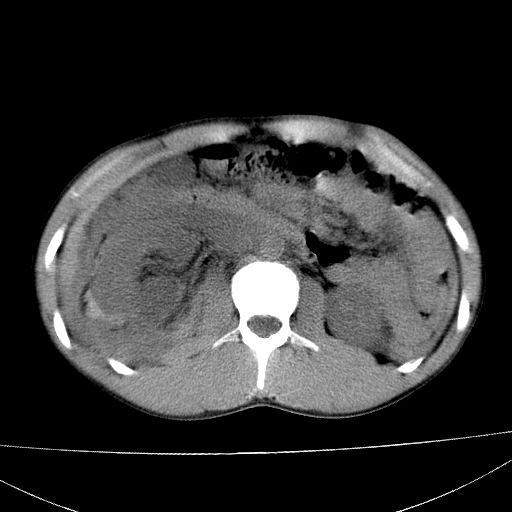

标题: CT15860:男,21岁,腹部外伤2小时伴胸疼。 [打印本页]

标题: CT15860:男,21岁,腹部外伤2小时伴胸疼。

肝脏及肾脏明显有损伤性改变并激发腹腔内积液(血),以肝脏撕裂及肾周积血显著。

1)肝破裂伴腹腔积液(血)。2)右肾破裂伴右肾包膜下及肾周血肿。3)腹部空腔脏器穿孔可能。4)右侧少量胸腔积液(血)。

肝肾挫裂伤,右肾周及包膜下血肿,腹腔积液,不排除空腔脏器穿孔,建议行增强检查

肝肾挫裂伤,右肾周及包膜下血肿,腹腔积液

肝、右肾包膜下血肿,右侧腰大肌及腹膜后血肿;腹腔少量积血;腹腔疑有少量游离气体伴肠破裂。

1肝挫伤伴腹腔积液。2右肾挫裂伤伴右肾包膜及肾后间隙肿血肿。3右肾脏周围的积气,十二指肠显示结构不清,考虑十二指肠降部破裂可能性大。